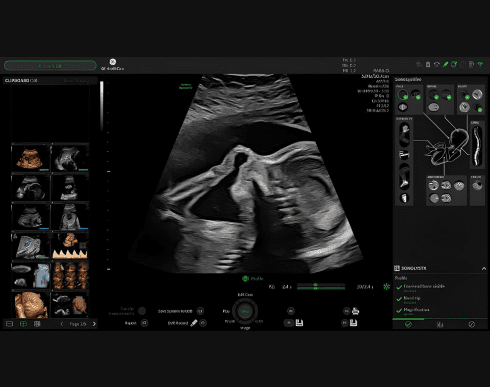

Функція УЗД апарату Sono List

Набір інструментів, які використовують штучний інтелект для ідентифікації анатомії плода на стандартних зображеннях, а потім автоматично анотують і вимірюють, якщо це застосовно.